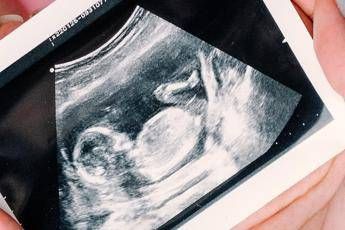

Sì all’ecografia nel primo trimestre per individuare precocemente eventuali malformazioni fetali, oltre a quella già raccomandata nel secondo trimestre. Sì anche all’offerta dello screening nel primo trimestre delle anomalie cromosomiche più frequenti, tra cui la sindrome di Down, mediante test combinato o test del Dna fetale, da proporre a tutte le donne indipendentemente dall’età. Raccomandata l’esecuzione della misura della distanza tra fondo dell’utero e sinfisi pubica ad ogni bilancio di salute a partire dalle 24 settimane gestazionali per valutare l’accrescimento fetale. Rimane non raccomandata l’ecografia nel terzo trimestre, salvo specifica indicazione clinica. Sono queste le principali novità introdotte dalla terza parte dell’aggiornamento della linea guida ‘Gravidanza fisiologica’, presentata durante un webinar a cura dell’Istituto superiore si sanità, al quale si sono iscritti 850 professionisti sanitari. Il documento è stato sviluppato dal Centro nazionale per la prevenzione delle malattie e la promozione della salute (Cnapps) dell’Iss, nell’ambito delle attività del Sistema nazionale linee guida (Snlg).

La possibilità di individuare già nel primo trimestre eventuali malformazioni consente alla donna e al partner di prepararsi consapevolmente alla nascita, valutare eventuali terapie intrauterine, programmare il parto in strutture adeguate alle necessità assistenziali neonatali o decidere per una interruzione volontaria della gravidanza, spiega l’Iss. “L’ecografia è uno strumento straordinario che ha rivoluzionato l’assistenza ostetrica. Tuttavia, non tutto ciò che è tecnicamente possibile è clinicamente appropriato e non tutto ciò che rassicura è realmente necessario”, afferma Serena Donati, responsabile scientifica dell’aggiornamento. “In Italia si eseguono in media 6 ecografie in gravidanza, senza differenze tra gravidanze fisiologiche e patologiche: ben oltre quelle raccomandate dalle linee guida nazionali e internazionali. Quando la pratica clinica si discosta dalle evidenze scientifiche – sottolinea – è fondamentale spiegare con chiarezza alle donne quali siano le indicazioni appropriate agli esami e, quando opportuno, avere il coraggio di dire che non sono necessari. Le linee guida rappresentano una bussola istituzionale per garantire qualità dell’assistenza, equità di accesso alle cure e sostenibilità del Servizio sanitario nazionale”.

Tra le principali novità dell’aggiornamento, la linea guida: raccomanda l’ecografia del primo trimestre per la diagnosi precoce di malformazioni fetali e per una corretta datazione della gravidanza; conferma l’offerta universale dello screening nel primo trimestre delle anomalie cromosomiche più comuni, introducendo l’esame del Dna fetale; sottolinea l’importanza del counselling, per rispondere in modo completo e trasparente ai bisogni informativi delle donne rispetto agli accertamenti per anomalie congenite; ribadisce il valore della percezione dei movimenti fetali come indicatore del benessere del feto; raccomanda la misurazione della lunghezza fondo-sinfisi come monitoraggio per la crescita fetale dopo la 24esima settimana; raccomanda di limitare ai soli casi con indicazione clinica l’ecografia per la valutazione della crescita fetale nel terzo trimestre.